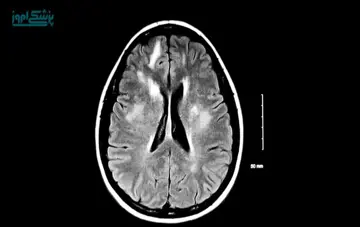

مطابق تعریف ، مولتیپل اسکلروزیس یا همان بیماری ام اس یک بیماری خودایمنی و التهابی است که سیستم عصبی مرکزی و اعصاب محیطی را درگیر می کند.